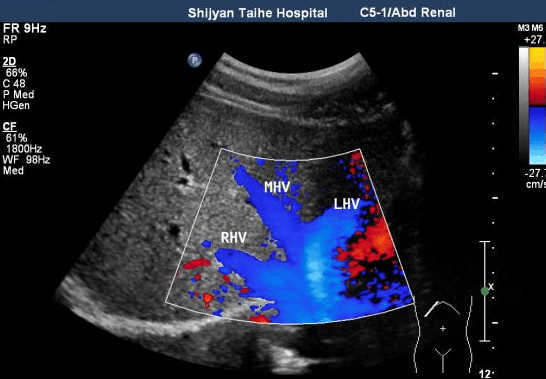

如果已经有肝炎或者肝硬化的症状,一定切记进行肝脏超声和AFP(甲胎蛋白)定期筛查;

即使没有症状,40 岁以上男性,50 岁以上女性,每年也应进行肝癌筛查(肝脏超声、AFP)筛查

如果是肝癌高危人群,建议每6个月做一次肝脏超声检查+血清甲胎蛋白(AFP)检查,如发现可疑病灶则考虑进一步做肝脏CT或核磁共振等。

肝脏超声